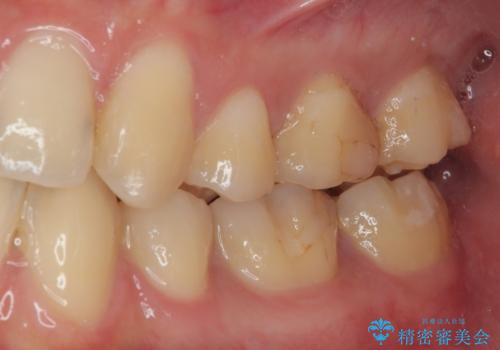

- 当院で矯正治療を終えて、左下が虫歯になっている気がするとのことで来院された患者様です。レントゲン検査の結果、コンポジットレジンによる修復箇所が複数行われており、詰め物の下に虫歯を認めました。

虫歯による不快な症状がなくなり喜んでいただきました。セラミックの被せものが入った後の違和感なく過ごせているそうです。矯正治療終了直後の被せもの治療なのでリテーナーの作成回数をできるだけ少なく迅速に行うことを考慮して治療を行いました。

今後、ホワイトニングを行う予定なので、患者様のご希望により、周りの歯に比べてあえて白い被せものを作成しました。